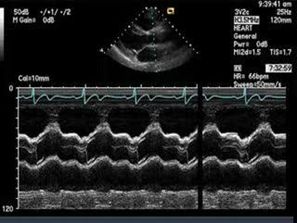

图 M型超声心动图

M型超声主要应用于心血管系统的检查,可以动态地了解心血管系统形态结构和功能状况,并获取相应的心血管生理或病理的技术指标。